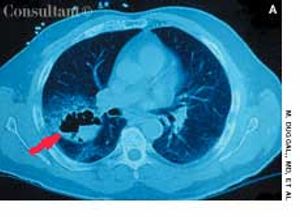

A 60-year-old woman with a 3-month history of cough, chest pain, and shortness of breath was brought to the emergency department. The patient denied any history of fever, chills, or rigors; she complained of mild hemoptysis for 1 week and a 9-kg (20-lb) weight loss during the last few months. The patient had smoked cigarettes for 40 years.